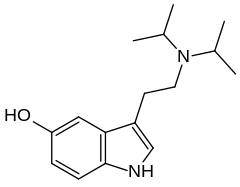

| Serotonin | Animals, plants | 5-OH | H | H | 5-hydroxytryptamine | 50-67-9 |

| Nω-Methylserotonin (norbufotenin) | Plants | 5-OH | H | CH3 | 5-hydroxy-N-methyltryptamine | 1134-01-6 |